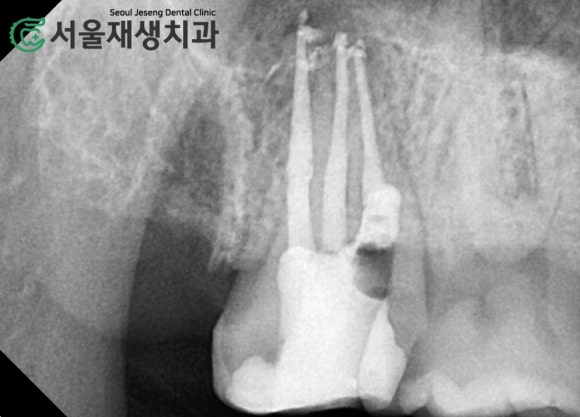

재신경치료가 무사히 완료되었습니다.

큰 장애없이 재신경치료가 무사히 완료되었습니다.

치료 전, 그리고 재신경치료가 끝난 직후에 촬영한 사진입니다.

이전 치료에서 미흡했던 부분들을

다시 한 번 꼼꼼히 청소 후 밀봉하였습니다.